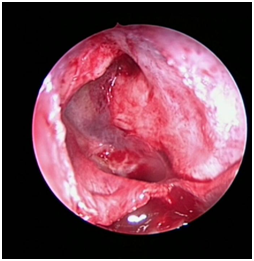

The patient was posted for endoscopic marsupialization of the mucoceles. The mucocele sac from ethmoid sinus was incised and the mucus was drained out (Figure 4 & 5) following which another mucocele sac was identified in the frontal sinus and was drained out (Figure 6 & 7) thus confirming the diagnosis of multiple mucocele introperately.

Figure 4 Intraoperative picture showing right ethmoidal mucocele.

Figure 5 Intraoperative picture taken after draining right ethmoidal mucocele.